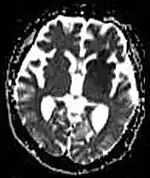

| Diffusion weighted (DWI) | Conventional | DWI | Measure of Brownian motion of water molecules.[17] | High signal within minutes of cerebral infarction (pictured).[18] |

|

Another application of diffusion MRI is diffusion-weighted imaging (DWI). Following an ischemic stroke, DWI is highly sensitive to the changes occurring in the lesion.[44] It is speculated that increases in restriction (barriers) to water diffusion, as a result of cytotoxic edema (cellular swelling), is responsible for the increase in signal on a DWI scan. The DWI enhancement appears within 5–10 minutes of the onset of stroke symptoms (as compared to computed tomography, which often does not detect changes of acute infarct for up to 4–6 hours) and remains for up to two weeks. Coupled with imaging of cerebral perfusion, researchers can highlight regions of "perfusion/diffusion mismatch" that may indicate regions capable of salvage by reperfusion therapy.